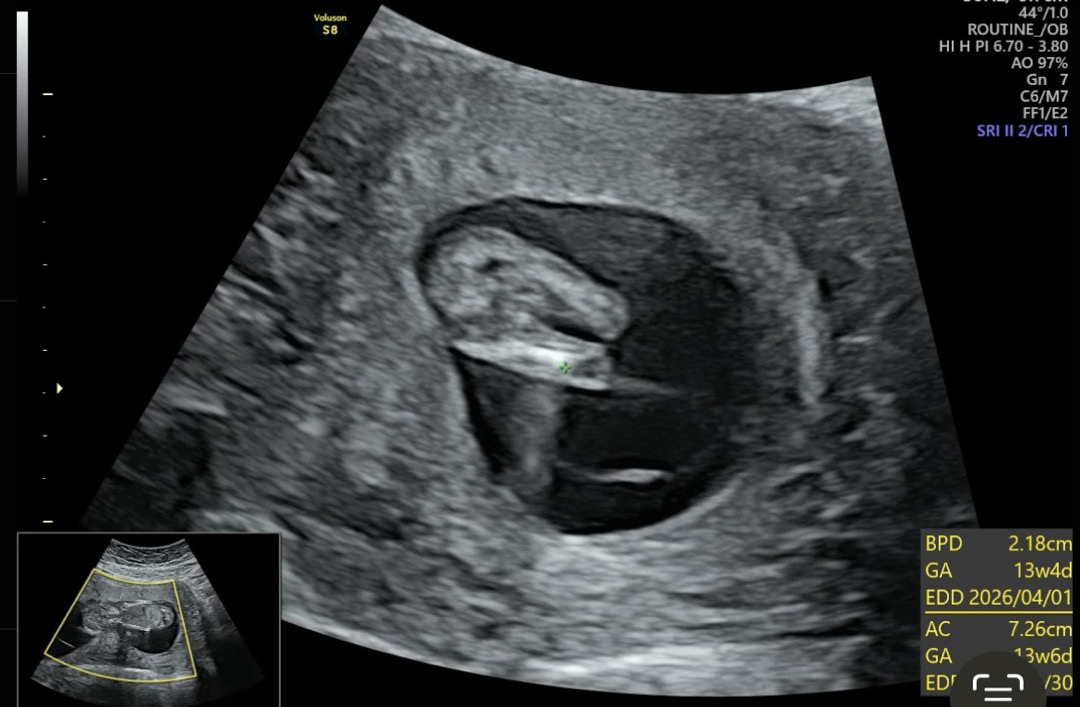

2차기형아하다가 성별볼려고 하는데 탯줄로 가려서 못봄이슈....성별은 때되면 볼수있다 생각하고 별 관심없다가 못보니깐 너무 궁금해졌어요!같이 한번봐쥬세용🥹13주때 초음파입니다!